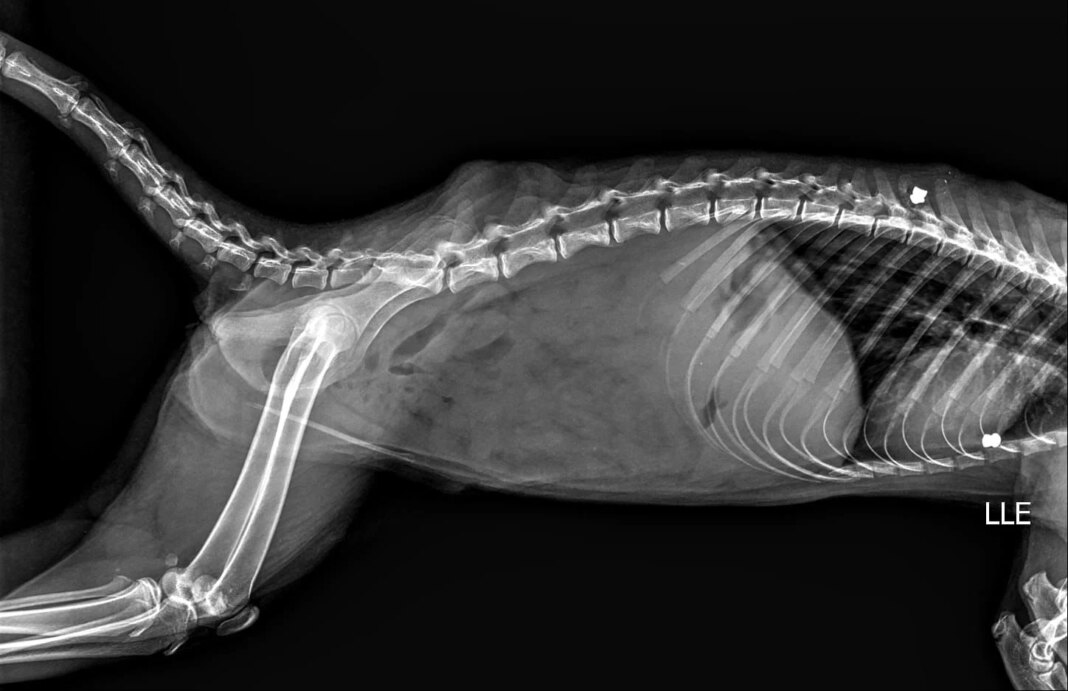

Há relatos de quatis atingidos por disparos de espingarda de chumbo, incluindo uma fêmea com projéteis alojados no corpo, inclusive na região da coluna vertebral.

Um caso com acompanhamento pela médica veterinária Melissa Campitelli revelou, após raio-x, identificou dois chumbinhos no corpo de um dos animais.